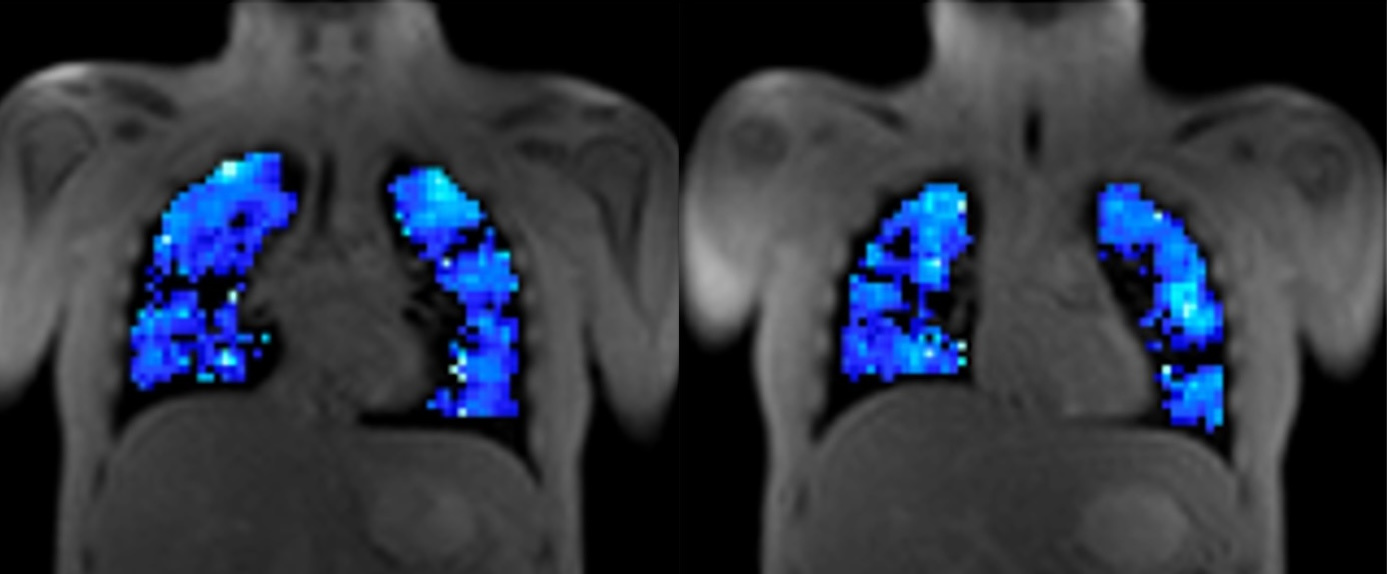

T2*-weighted oxygen-enhanced pulmonary MRI in COPD is linked to resting and exertional functional measurements

Why it matters: First demonstration of Bioxydyn's dual echo T2*-weighted imaging protocol applied in COPD

Oxygen-enhanced MRI (OE-MRI) is a non-invasive and non-ionising imaging method that uses oxygen as an MR imaging agent, which is delivered to the patient in the scanner. OE-MRI can be deployed on most hospital scanners.

Lung OE-MRI monitors the delivery of oxygen to patients' lungs. The acquired quantitative imaging biomarkers relate to regional lung ventilation and gas diffusion. Bioxydyn has extensive experience in deploying OE-MRI in diseases including chronic obstructive pulmonary disease (COPD), cystic fibrosis, primary ciliary dyskinesia (PCD), interstitial lung disease (ILD), lung cancer, and asthma.